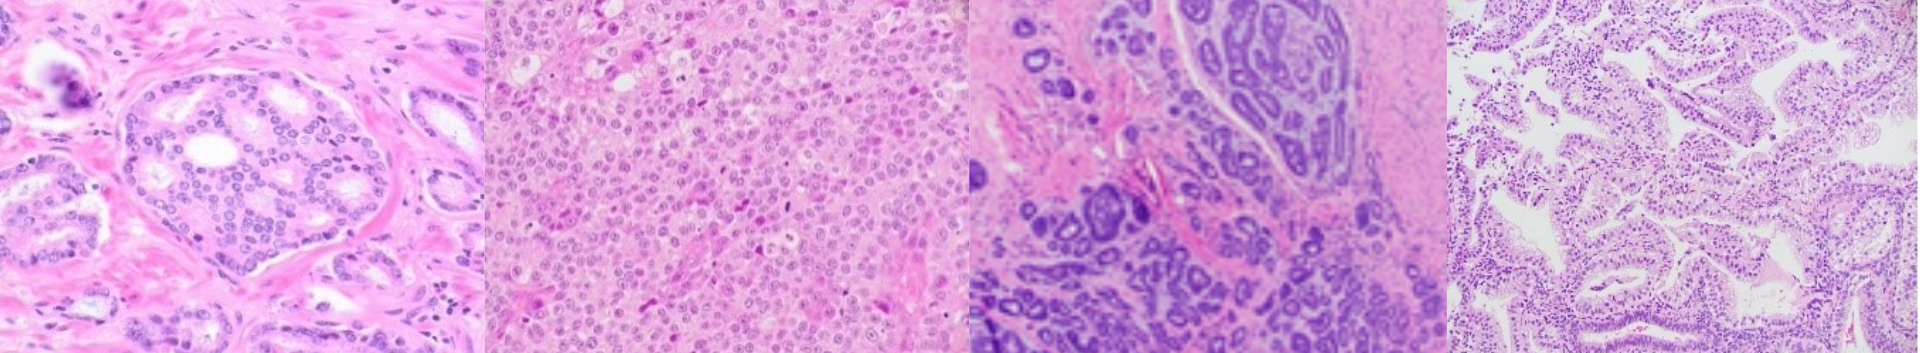

The Division of Anatomic Pathology at the University of Alabama (UAB) Medical Center, Birmingham, offers a one-year Fellowship/Instructorship position in Diagnostic Surgical Pathology with advanced comprehensive training experience, graduated responsibilities, and sign out privileges. There are approximately50,000 specimens per year, which cover the entire breadth and depth of Pathology. It provides service to O’Neal Comprehensive Cancer Center at UAB, supports the liver and kidney transplantation program, and provides daily consultations to the UAB –affiliated peripheral medical Centers in the State of Alabama. The Anatomic Pathology division is subspecialized with majorsections including GI/liver Pathology, Breast Pathology, GYN Pathology, GU Pathology, Musculoskeletal Pathology, Head and Neck Pathology, Pulmonary Pathology, and Renal Pathology. Tailoring the fellowship with subspecialty focus in up to three aforementioned (Breast, GYN, GU, ENT, Bone/Soft tissue, GI) areas is possible. Opportunities for elective rotations in other services including Pediatric Pathology at Children’s of Alabama (adjacent to UAB Hospital)and Molecular Pathology exist. The responsibilities include covering frozen sections, active participation in interdepartmental tumor boards and conferences, and teaching residents and medical students. Fellows are highly encouraged to participate in ongoing basic, translational or clinic-pathologicresearch projects in collaboration with more than 90 faculty members in the Department. Rotations are entirely at The University of Alabama Hospital.